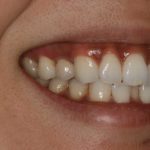

This patient had a implant place to replace a tooth which had been removed due to infection.